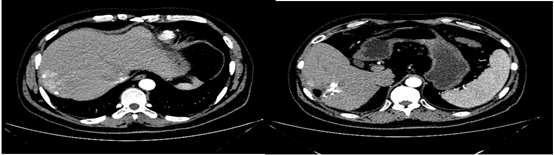

2019年1月17日(术后1个月)入院复查,影像学见疑似复发病灶。                         图片

图:影像学检查(2019-01-17)

遂予肝动脉化疗栓塞(TACE)治疗,行数字减影血管造影(DSA)可见肝右叶多个结节状肿瘤染色,明确肝左、右动脉分支为肿瘤供血动脉,判定为外科术后复发。

图片

图:第一次TACE治疗

2019年2月21日以碘油5 ml+0.9%氯化钠20 ml+表阿霉素10 mg+雷替曲塞1支稀释后灌注方案行TACE治疗。后复查肝增强CT,未见明显强化,对比2019年1月病灶略缩小,初次TACE治疗达SD。